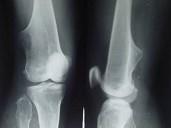

女,15岁,大腿远端可摸到肿块,无明显疼痛,请结合研提供图像,选择最佳答案()A.骨质增生B.软骨瘤C.骨肉瘤D.骨瘤E.骨软骨瘤

问题 女,15岁,大腿远端可摸到肿块,无明显疼痛,请结合研提供图像,选择最佳答案()

选项 A.骨质增生 B.软骨瘤 C.骨肉瘤 D.骨瘤 E.骨软骨瘤

答案 E